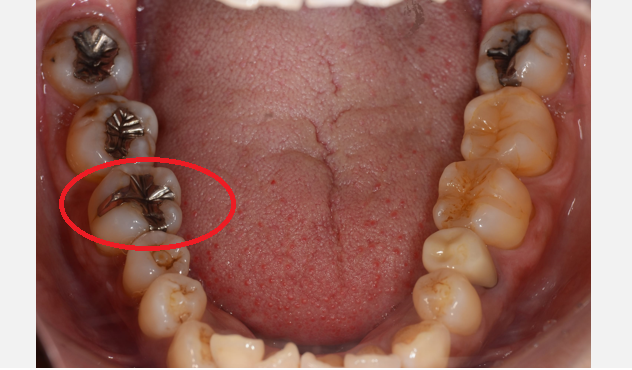

CASE1

| 年齢 ・ 性別 |

39歳・女性 |

|---|---|

| 主訴 | 左下6番 |

| 治療 内容 |

セラミックインレー |

| 治療 費用 |

55,000円 (2022年2月現在) |

| 治療 期間 |

2週間 |

| リスク ・ 副作用 |

・虫歯が深い場合、装着後に「しみる」「痛む」といった症状が残ることがあります。 ・装着直後、かみ合わせに違和感を感じることがあります。 ・セラミックは陶器のため、割れることがあります。 ・型どりから装着までの間、仮ふたでお過ごしいただくことになります。 |

| 治療方針 | 右下6の銀歯が二次的な虫歯になっていたので、銀歯を外して詰め物の型どりを行う |

| 特記事項 | 見た目も気にされていましたが、再度虫歯にならないようにセラミックインレーにかえました。 |

| 担当者所見 | 就寝時にマウスピースを使用しているので、そのままつかってもらう。 メンテナンスメンテナンスを行って、状態確認をする。 |

Before

After